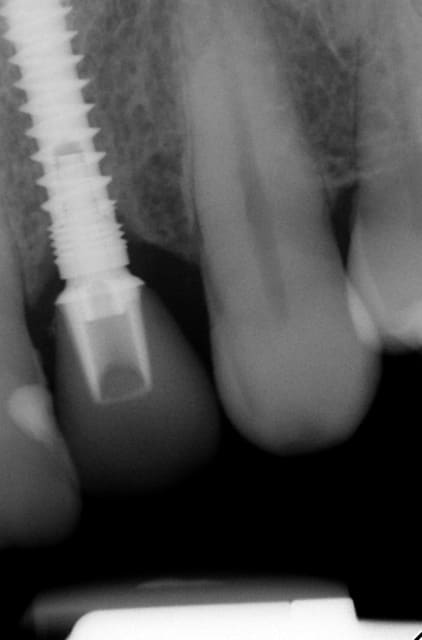

Merci pour tes questions. Si tu as une gencive "normale" (2-3 mm) ( avec le foret on peut savoir grâce aux mesures ) tu arrêtes à implanter si le truc en métal (je ne sais pas en francais en allemand Einbringhilfe) arrive à la gencive. Si la gencive fait plus de 3mm tu pousses un peu plus (le début de la fenêtre du Einbringhilfe est à un millimètre , la fin de la fenêtre = 3mm ) ...on vérifie avec une petite radio (pas OPG) .

Oui sans condenser juste en flapless ca serai moins évident. Pour moi-même en condensant j´ai besoin de 1 mm buccal minimum(plus il y a mieux c´est) mais dans ma pratique et celles mes confrères ca fonctionne et cela dure dans le temps depuis 16 ans.

En dessous il y a des photos, dans une on voit (troisième) qu il n y a pas de resorption de l´os après 14 ans, ce que l´on voit c´est l´os très fin condensé sur l´implant.